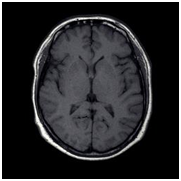

Neuroftalmology service was consulted and during interrogatory patient refers to consume fragrances the last 20days because he had no money to buy ethanol, and for this reason and symptoms of methanol toxicity diagnosis was suspected. At hematic biometry he presented normochromic normocytic anemia (Hb 8.7g/dL), in blood chemistry hyperglycemia with 331mg/dL. Cerebrospinal fluid exam and urinalysis were normal. Exam of methanol in urine was positive with 35mg/L. Simple Cranial Magnetic Resonance and angio-resonance were normal (Figure 4).

Figure 4 Contrasted Magnetic Resonance. First image T1 (left), second T2 (center) and third (right) without evidence of compression, vascular lesion or ventricular dilation.